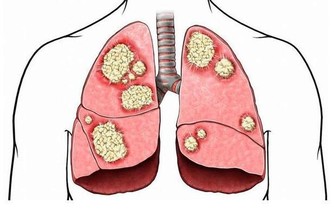

葫蘆素(英語:Cucurbitacin)是從中藥中提取,可治療肝炎及肝癌,存在於深綠色果類或果蒂部位,但誤食過量會有噁心、嘔吐、腹瀉等胃腸道症狀

人們在食用黃瓜時,因黃瓜把兒味苦而往往將其丟棄。其實,這種苦味是由其中含的一種叫葫蘆素的物質引起的,而葫蘆素C是難得的排毒養顏物質。更重要的是,葫蘆素可阻止肝細胞脂肪變性,抑制肝纖維增生,從而可預防原發性肝癌。

1、抗腫瘤

黃瓜中含有的葫蘆素C具有提高人體免疫功能的作用,達到抗腫瘤目的。此外,該物質還可治療慢性肝炎和遷延性肝炎,對原發性肝癌患者有延長生存期作用。